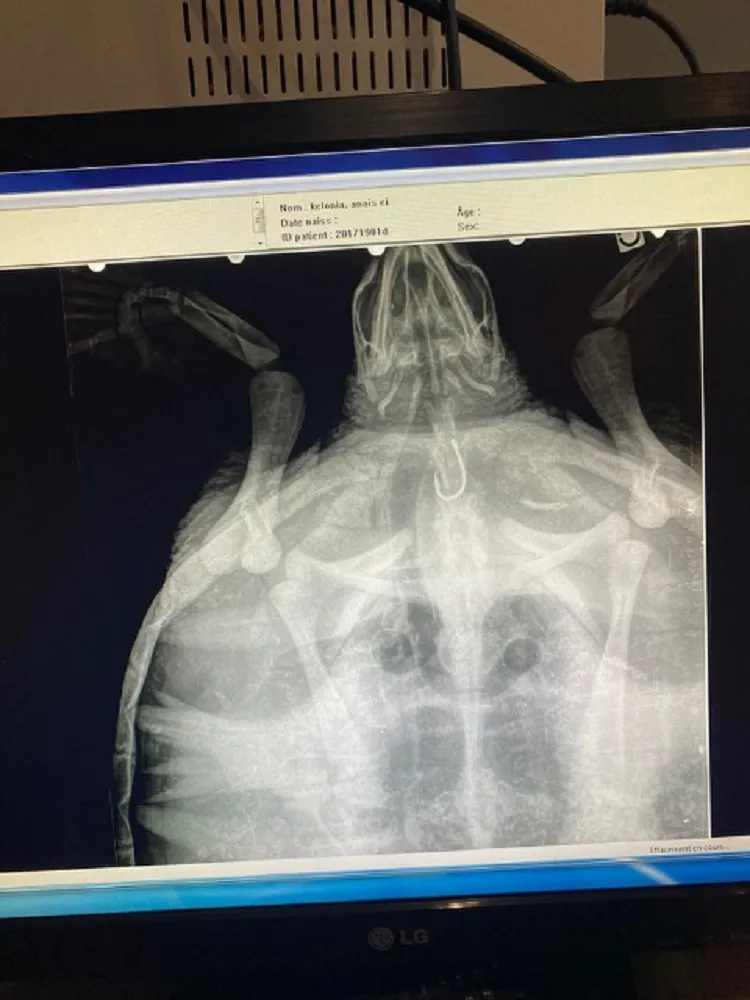

Celle-ci sera opérée pour retirer l’hameçon cet après-midi.

La récupération de la tortue par le Centre de soins de Kelonia devrait éviter que cette tortue subisse le même sort que celle récupérée fin décembre morte sur la plage de Souris Chaude. Elle aussi avait avalé un hameçon et était morte faute de soins. 80% des tortues ayant avalée des hameçons et récupérées par le Centre de soins survivent (c’est moins de 20% de survie en cas de collision avec un bateau).